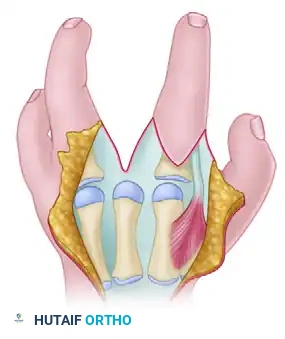

Bone transposition in progress: The fasciae of the first dorsal interosseous and adductor pollicis are released.

Detailed view of the bone transposition and the necessary muscular releases required to achieve a tension-free shift.

- Completion of Transposition: Once the osteotomy is performed and the soft tissues are released, the index ray is secured to the third metacarpal base, and the thumb is brought into full palmar abduction.

Transposition of the index ray and the release of the thumb adduction contracture are completed.